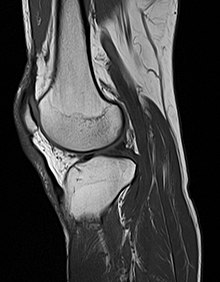

Muscoloskeletal

Conceptual images from various sources